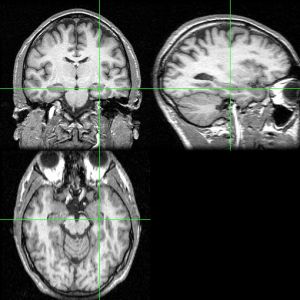

图片

- Hippocampus and seahorse cropped.JPG

大脑的海马区(左)和海马(右)。